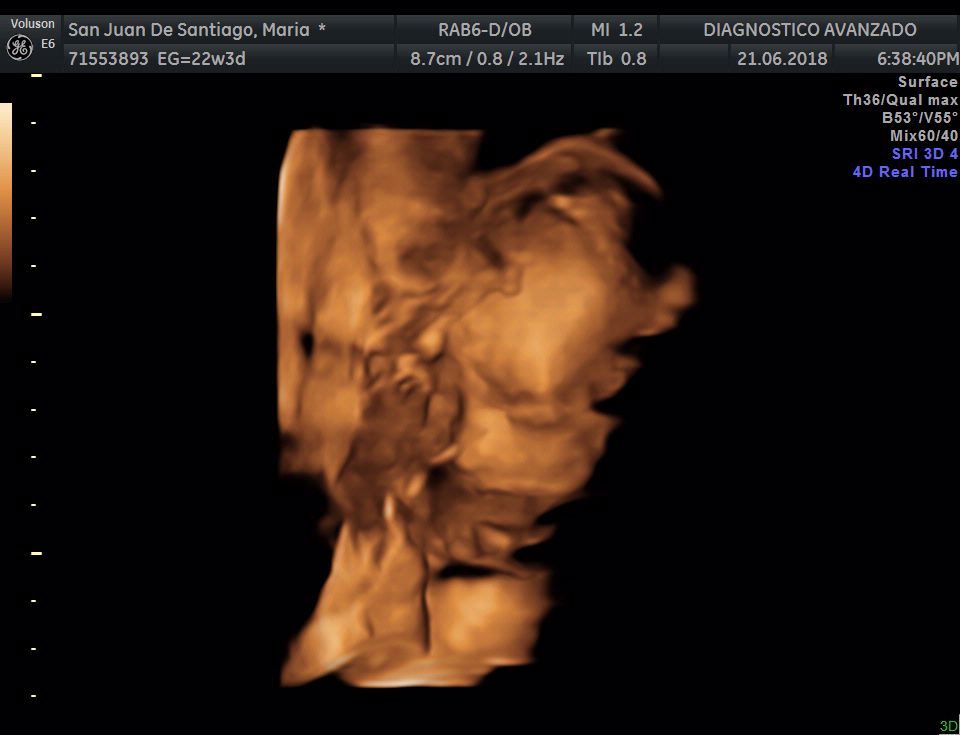

¡Hola a todos! Hoy hemos ido a hacer la tradicional ecografía 3D de la niña, os dejamos todo el material (aunque es un poco demasiado).